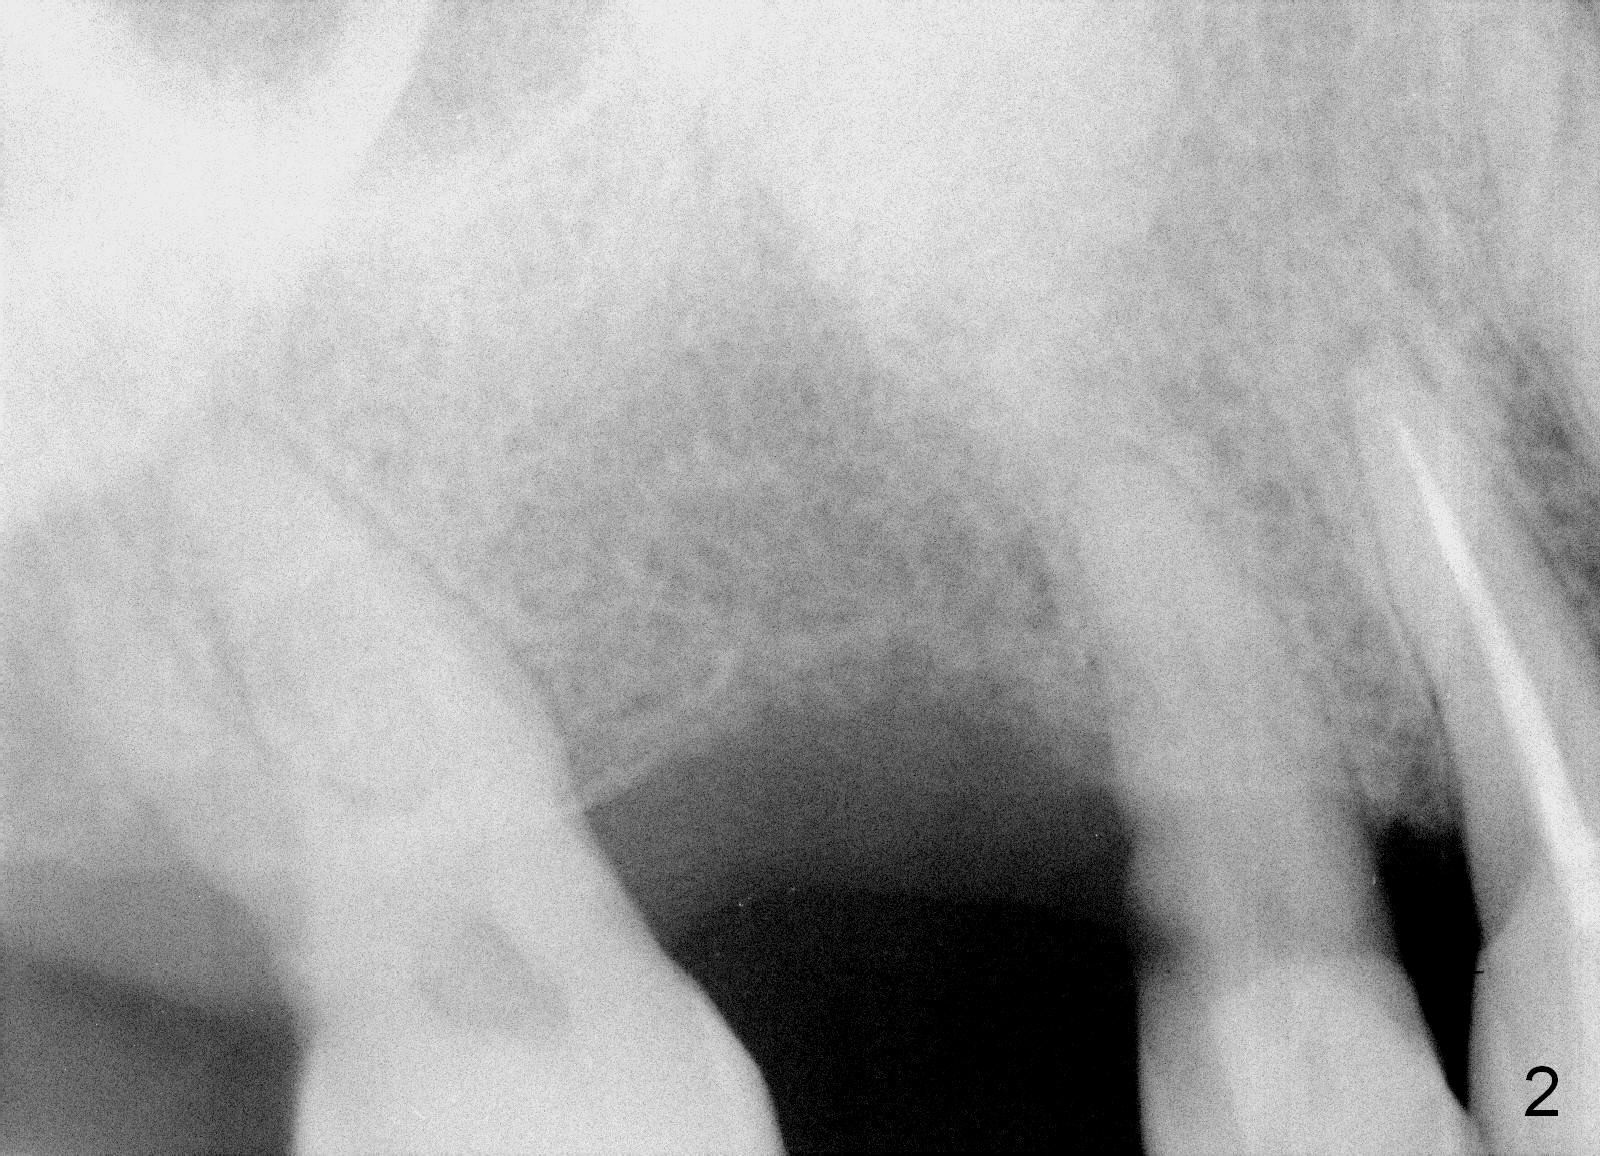

Although the bone height allows a 14 mm long implant, the initial depth of osteotomy is 10 mm. Prepare the SM cassette. The advantage of using 4 mm shorter drill is that it is easy to change trajectory if it is not right, determined by the 1st intraop PA.

If the bone density is found to be low while using the 2 mm pilot drill, use bone expanders until 2 sizes smaller than the final diameter (Fig.3,4). Use the 5 mm implant positioner to preliminarily determine the diameter of the implant. Place the initial osteotomy slightly palatal. Check whether the osteotomy shifts buccally after each step of bone expansion or drilling.